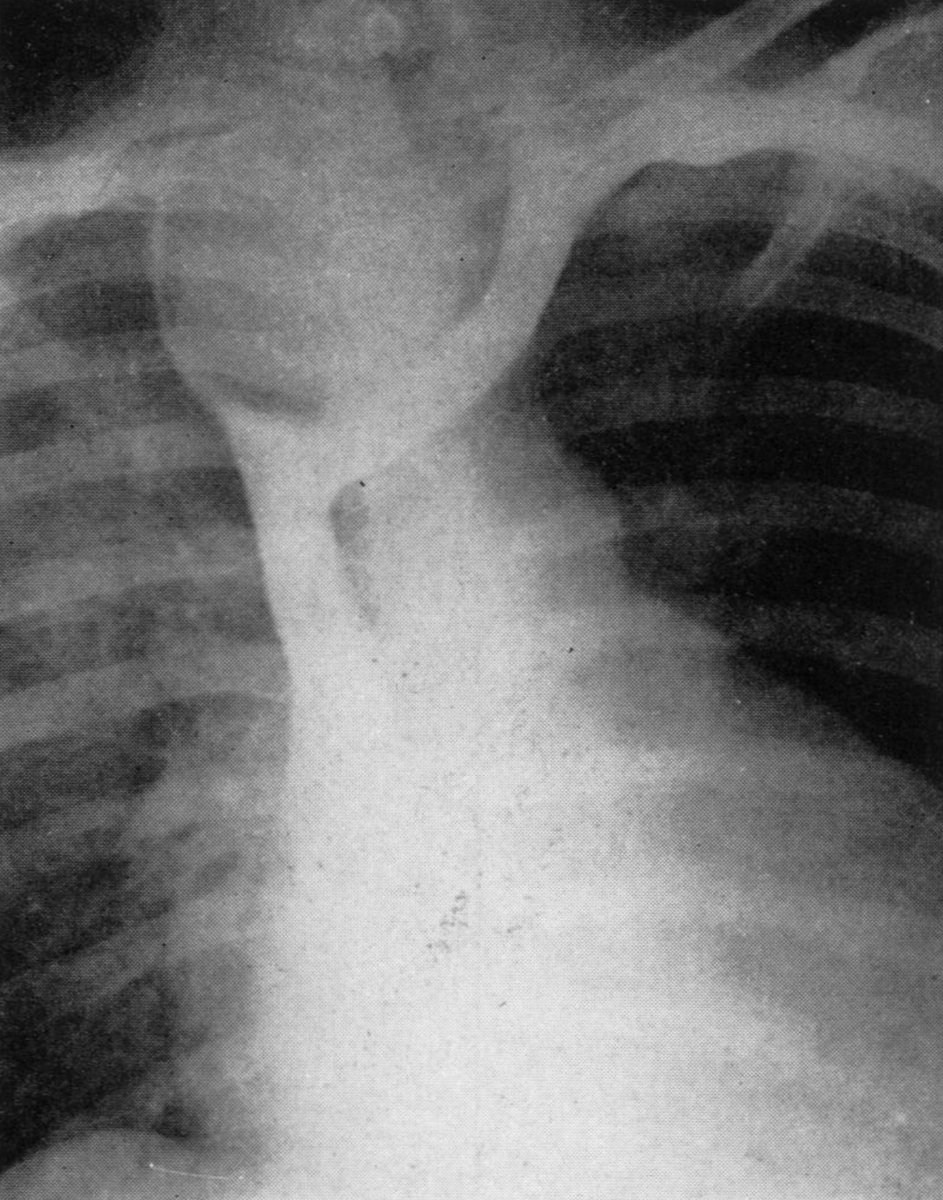

I’ll end with a story that’s been passed from person to person as Cooley lore. While he was on his rounds, one of DeBakey’s cardiologists asked him if he could spare a moment and take a look at an x-ray. There was a suspicious shadow in the chest along the aorta.

He asked Cooley if he had seen an aneurysm in this particular area before.

“No,” said Cooley, “and neither has anyone else because that’s not an aneurysm.”

The cardiologist hemmed and hawed and begged his pardon and added that DeBakey thought otherwise. “You can beg anything you want,” said Cooley dismissively, “but it won’t make that an aneurysm.”

“Dr. Cooley, I think you’re mistaken this time,” the cardiologist insisted. Cooley offered to bet him a hundred dollars. He declined and said that he wasn’t a betting man. “Well,” announced Cooley with an air of finality, “If that thing’s an aneurysm, I’ll eat it!”

The next morning Cooley received a phone call from the cardiologist’s secretary. “The doctor asked me to tell you to get your knife and fork ready. Do you remember the x-ray from yesterday? Dr. DeBakey just operated on him and took out an aneurysm.”